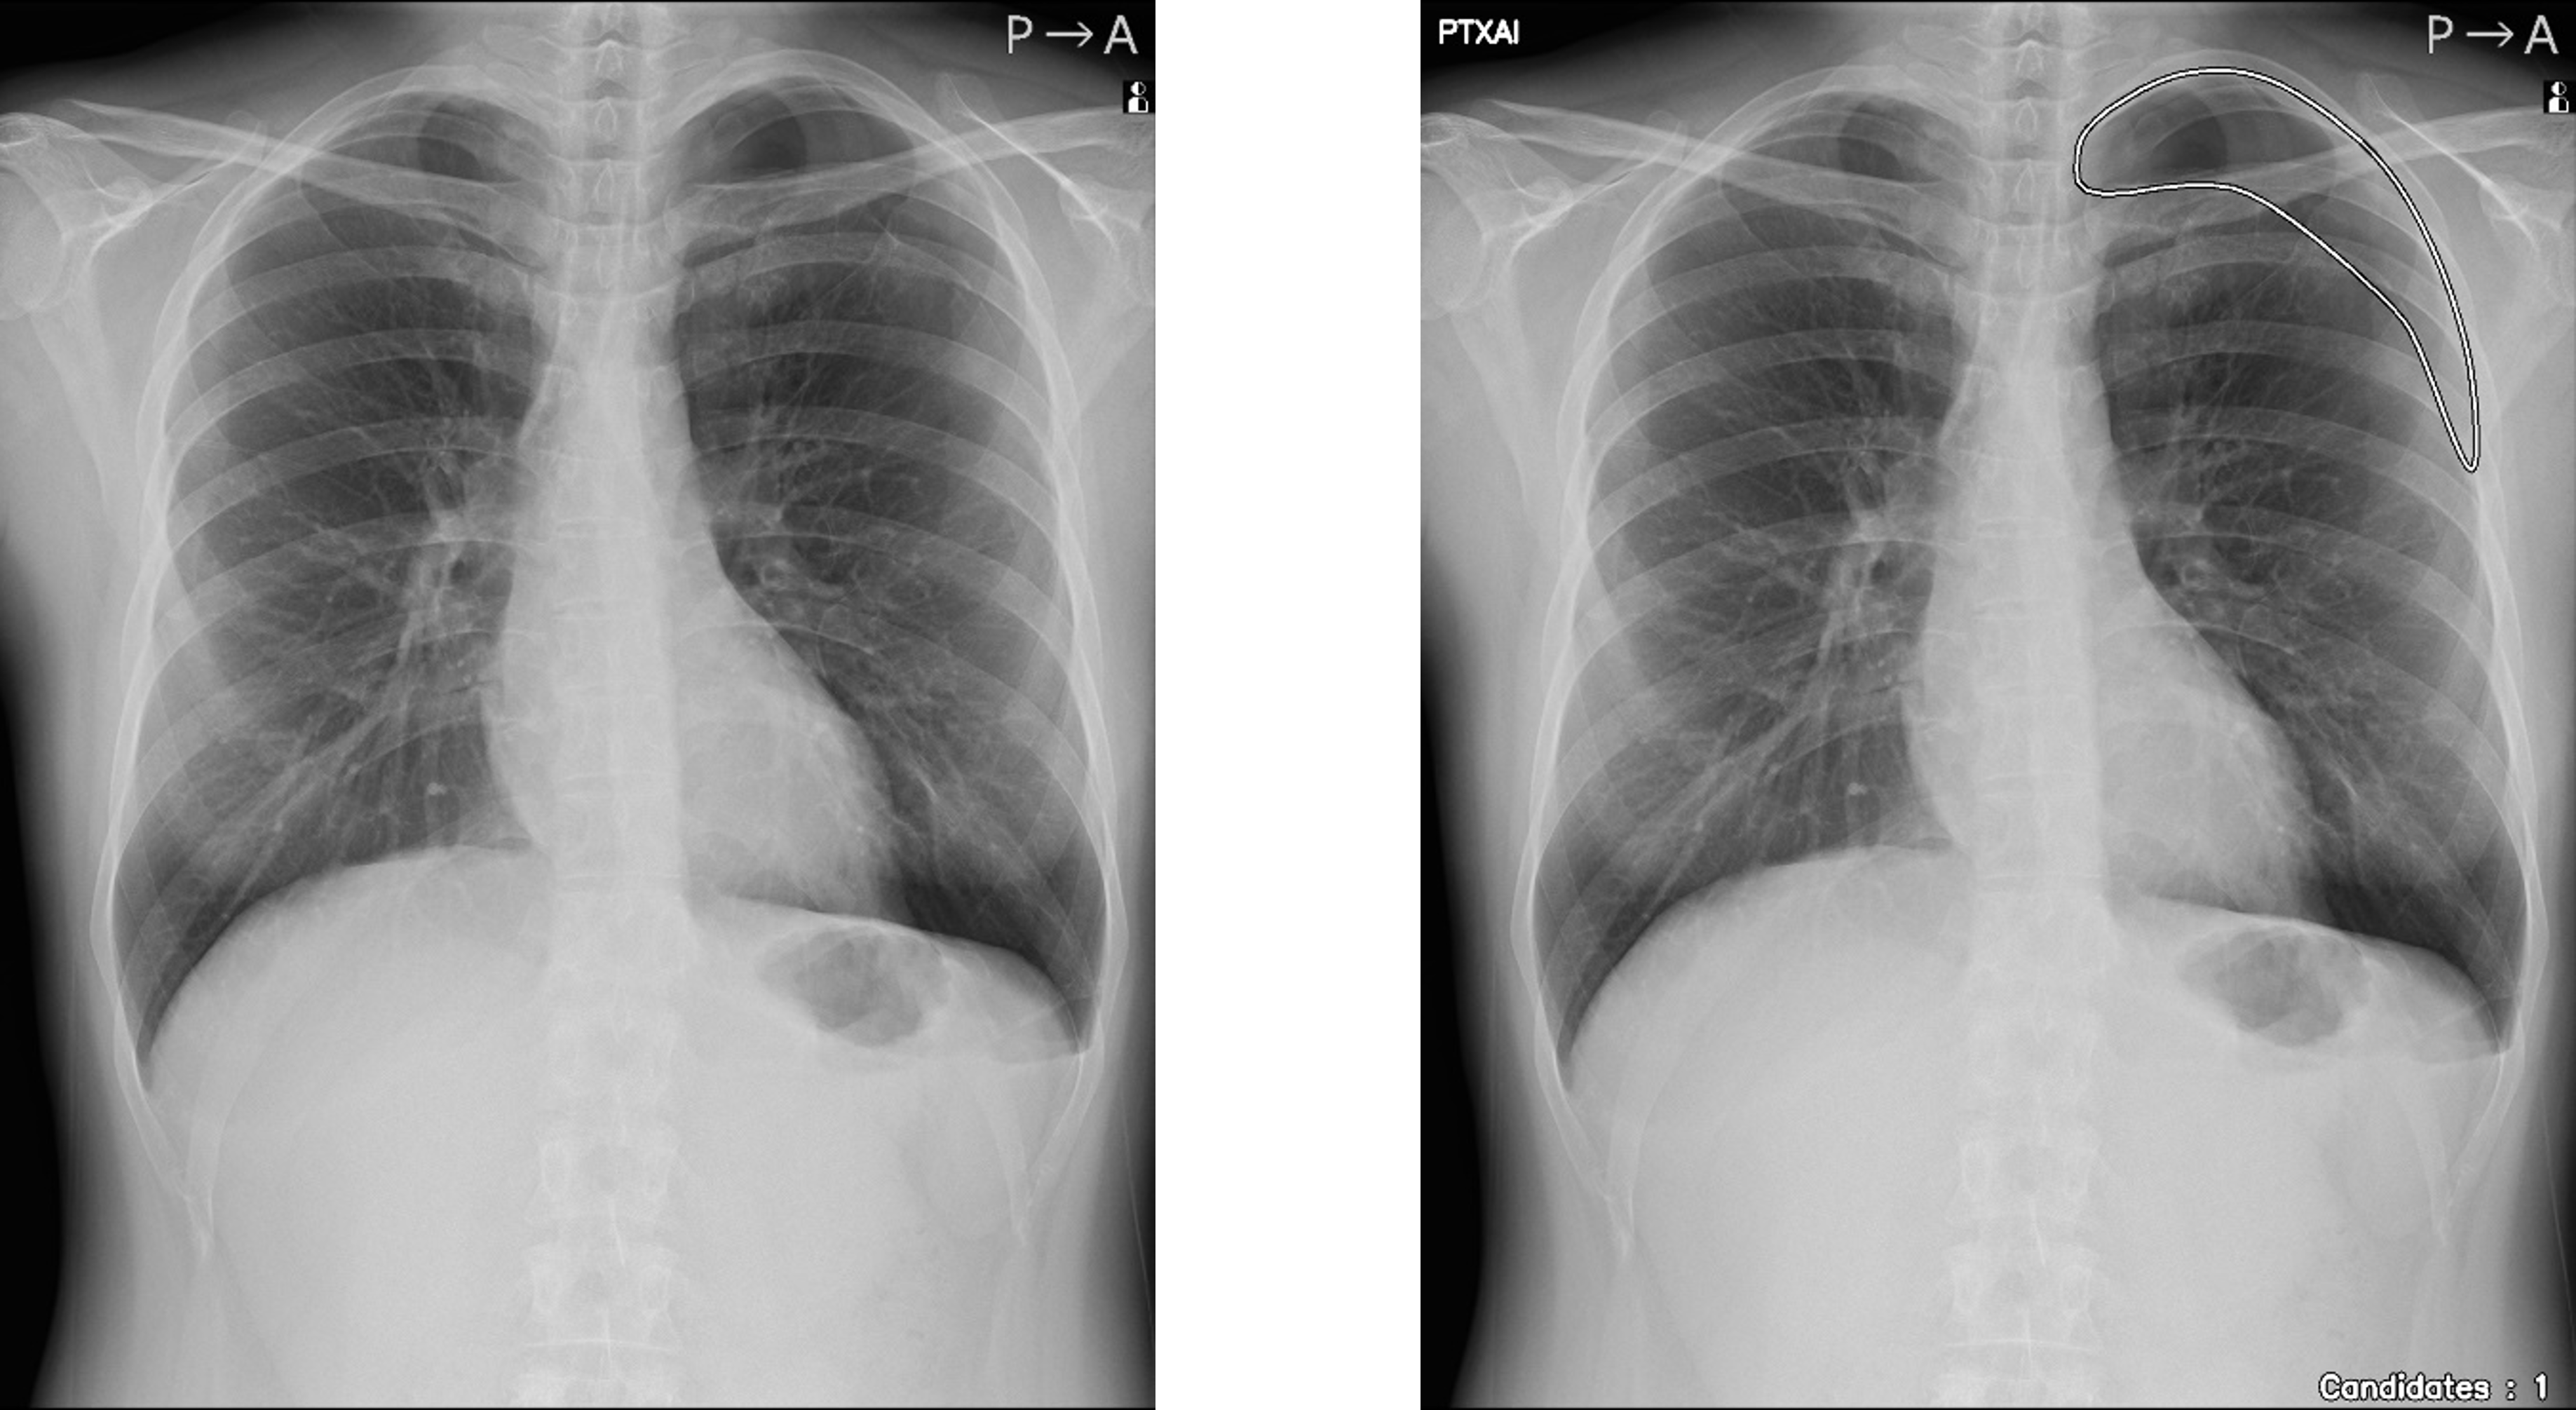

人のレントゲン写真 オリジナル画像

オリジナル画像

人のレントゲン写真 気胸の検出領域を表示

気胸の検出領域を表示

「CXR Finding-i 気胸検出タイプ」は、胸部単純X線画像をAI※2で解析することで重要所見である気胸の候補を迅速に検出し、候補領域を画像上に表示することで見落とし防止を支援します。病変検出性能を示す指標である感度※3は95%と高い水準を実現していることに加え、気胸が存在しない画像をAIが正しく陰性(気胸なし)と判断した割合を示す特異度※4は96%であり、病変を見逃さないようにしつつ偽陽性も抑制した高精度の検出性能が特長です。